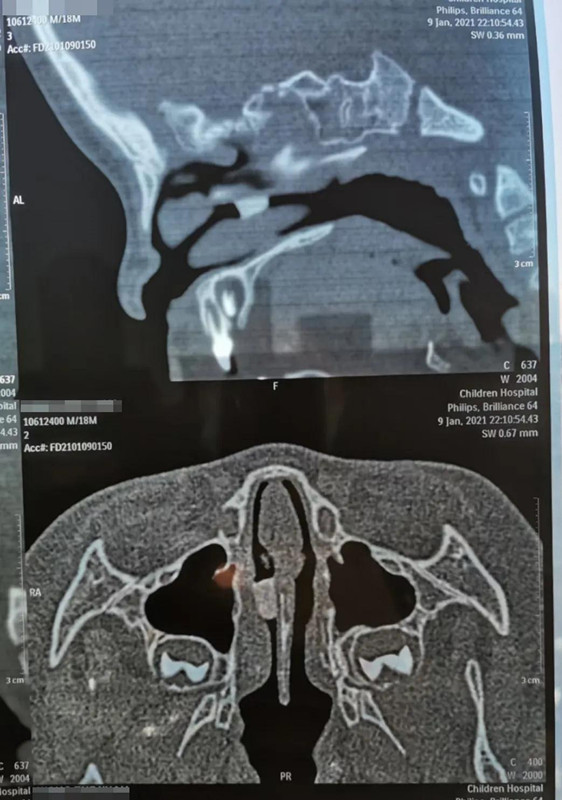

1月9日晚10点多,在夜深人安睡的时候,18个月男宝帅帅(化名)哭闹着被妈妈抱进蜜桃视频 就诊。妈妈说,晚上5点多,帅帅打碎了瓷鸭子玩具,偷偷把瓷鸭子嘴塞进鼻子里。经鼻腔三维CT重建,发现异物在右侧鼻腔较深位置,需次日全麻下手术取出。

取出8mm长异物